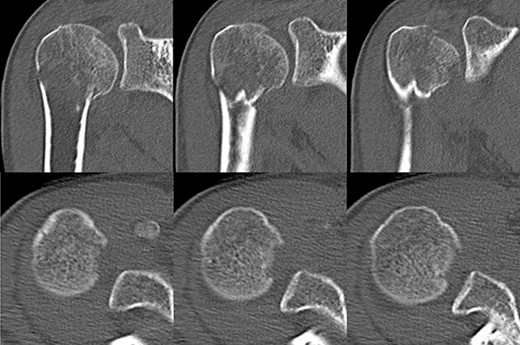

A 39-year-old man was transported via ambulance after being hit by a car. The radiographs revealed a one-part proximal humeral fracture with displacement at the surgical neck (Fig. 1). However, computed tomography (CT) revealed humeral head impression fracture and lesser tuberosity fracture in addition to a surgical neck fracture (Fig. 2). In addition, 3D-CT revealed that the collapse occupied approximately 20% of the articular surface with no glenoid defect (Fig. 3). Therefore, we first performed arthroscopic-assisted reduction and internal fixation of the humeral head impression fracture, followed by open reduction and internal fixation (ORIF) of the proximal humeral fracture.

Original CT scan showing impression fracture and surgical neck fracture.

3D-CT scan showing approximately 20% of articular surface of the right proximal and no glenoid defect, indicating no posterior shoulder dislocation.